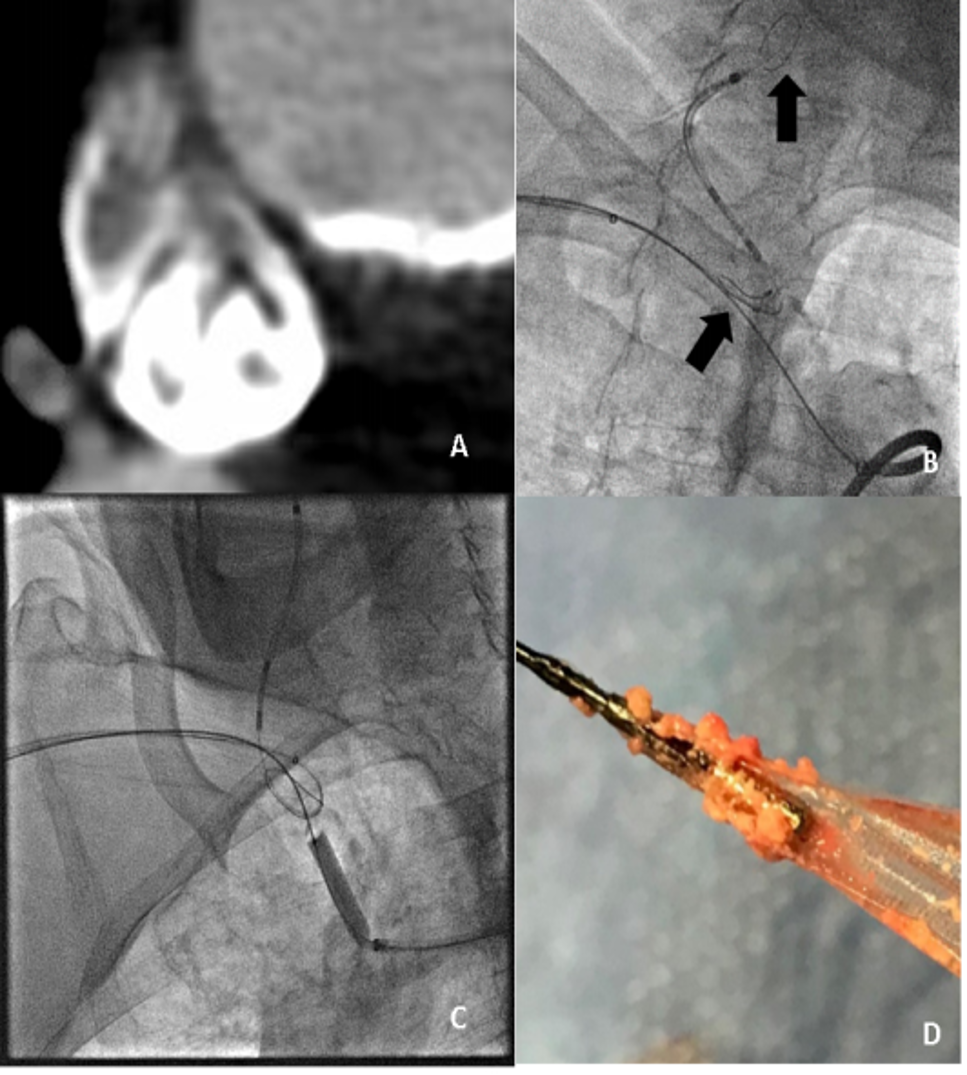

① 双滤网保护(Ann Vasc Surg 2020)

77岁男性,无名动脉狭窄95%,经桡动脉放置双滤网(颈内+锁骨下),股动脉植入覆膜支架

术后滤网捕获大量斑块,上肢压差从50mmHg降至2mmHg。